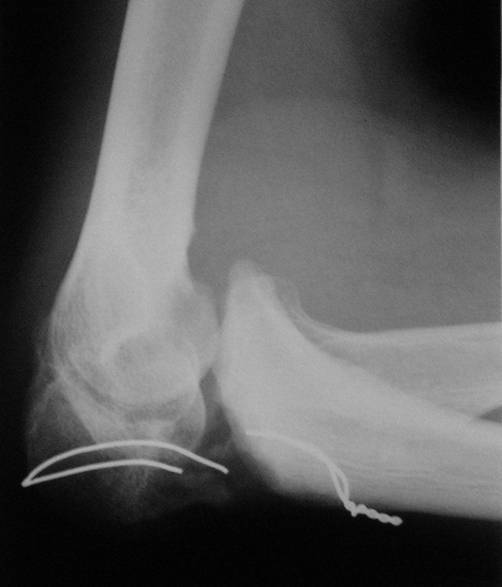

Уважаемые коллеги! Пациент 34 лет. Человек физического труда. Восемь месяцев назад в отделение сочетанной травмы был произведен остеосинтез локтевого отростка проволокой. В последующем r занимался разработкой сустава. Когда понял, что восстановить сустав не удастся, обратился за помощью. Предполагает, что после операции функция сустава восстановится полностью. Мы думаем выполнить операцию в два этапа: 1. Первый этап - аппаратом вправить предплечье 2. Второй этап - остеосинтез локтевого отростка спонгиозным винтом, или пластиной, или по Веберу с костной аутопластикой.Помогите советом. С уважением Н.Петров

По представленному снимку можно сделать заключение не только о несостоятельности МОС и технических погрешностях, допущенных при его наложении, но сейчас ГЛАВНЫЙ вопрос равномерного лизиса отростка. Он прозрачен на снимке, а значит лишен питания (частично или полностью - это Вам надо выяснить!). Следовательно можно думать о аваскулярнои некрозе л.отростка, следовательно - костная аутопластика необходима, но какая? Я думаю только несвободная, обязательно на сосудистой ножке, или если свободная, то с включением питающего трансплантат сосуда в одну из возвратных артерий локтевого сустава.

А> вопрос равномерного лизиса отростка. Он прозрачен на снимке, а

Это аваскулярные фрагменты как раз выглядят склерозированными. А остеопороз говорит о сохраненном кровоснабжении.